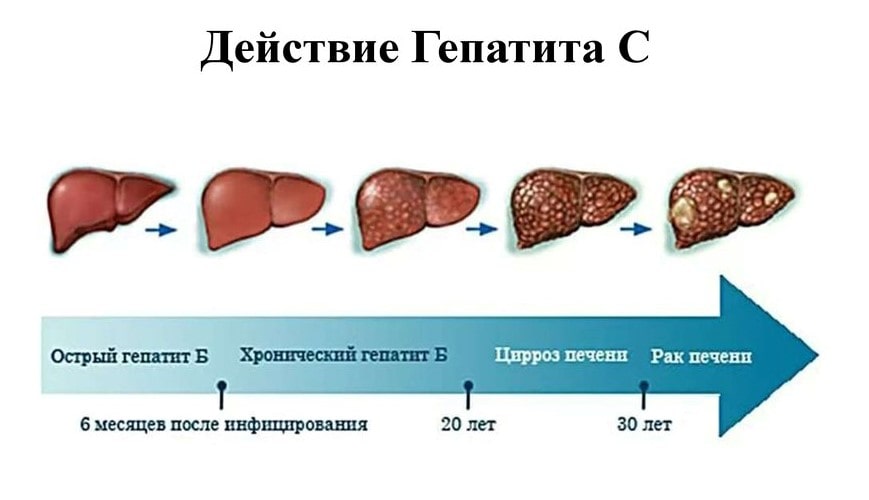

Изображения заболеваний печени: признаки и симптомы